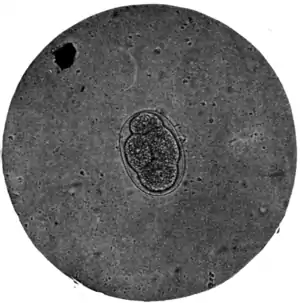

Fig. 173.—Ovum of A. duodenale, x 250. (Photograph by Dr. J. Bell.)

The ova of Ankylostomum duodenale (Fig. 168, b) contrast very markedly with both the foregoing, particularly in the matter of colour. Trichocephalus and ascaris ova are invariably dark and bile-stained; those of the ankylostomum are beautifully clear and transparent; they measure 55 μ to 65 μ by 32 μ to 43 μ; have a regular, somewhat elongated oval form, with a delicate, smooth, transparent shell, through which two, or four, or eight light-grey yolk segments can be distinctly seen. It is well to search for these ova soon after the fæces have been passed; otherwise, owing to the rapidity with which, in favourable circumstances, development proceeds, the embryo may have quitted the shell and the egg be no longer visible.

Reproduction and mode of infection.—The female ankylostomes produce a prodigious and never-ending stream of eggs (Fig. 168, b), which pass out in the fæces. As already stated, while in the body of the host the development of the embryo does not advance very far; but on leaving the human host it proceeds, in suitable circumstances, so rapidly that in one to two days a rhabditiform embryo (0·2 mm. by 0·014 mm.) is born. This minute organism (Fig. 179) is very active, voraciously devouring what organic matter it can find and, for a week, growing rapidly, to 0·56 mm. by 0·024 mm. (Fig. 180).